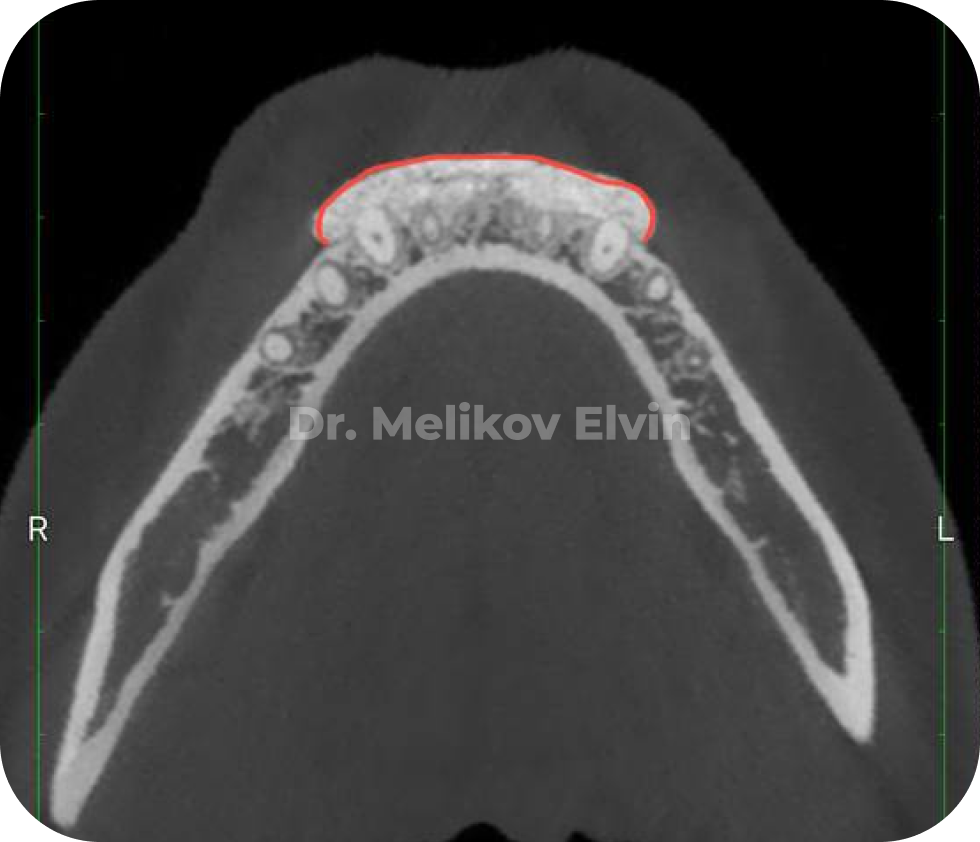

На снимках можно увидеть воссозданный объём наружной кортикальной пластинки в проекции корней зубов.

После костной пластики на нижней челюсти